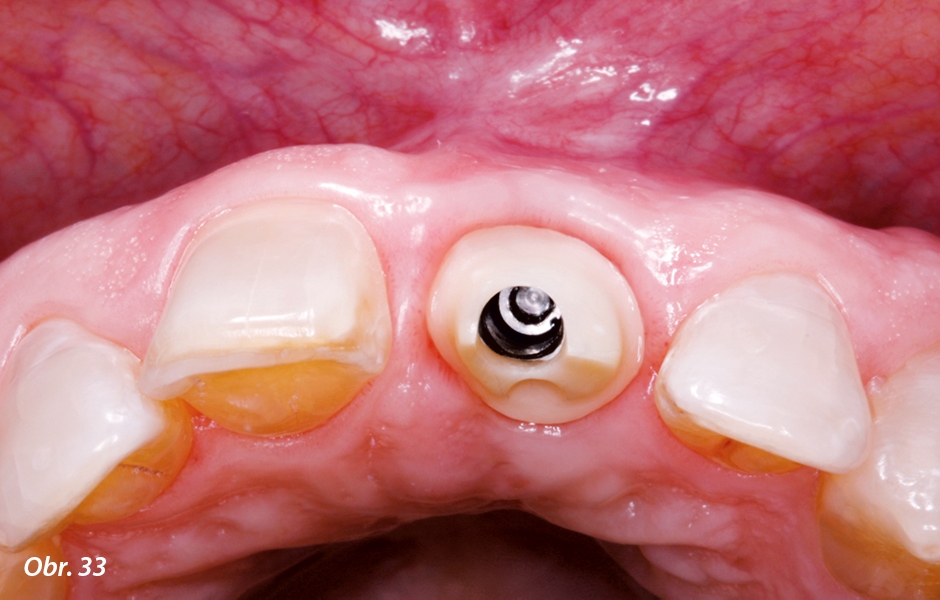

Po sejmutí provizorní korunky a provizorní fazety byl definitivní individualizovaný abutment přenesen pomocí laboratorně zhotoveného klíče na nitrokostní implantát a přišroubován momentovým klíčem (obr. 31 a 32). Abutment představoval v subgingivální oblasti přesnou kopii dlouhodobě provizorní korunky a podepřel tak periimplantární měkké tkáně stejným způsobem jak v horizontálním (obr. 33), tak i ve vertikálním směru (obr. 34).

Individuální abutment perfektně podepřel periimplantární měkké tkáně v horizontálním směru

Rovněž ve vertikálním směru byly díky abutmentu perfektně podepřeny měkké tkáně. To bylo jasně patrné na aproximálních papilách.